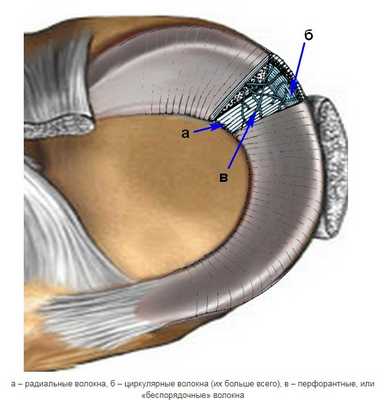

Виды повреждения мениска